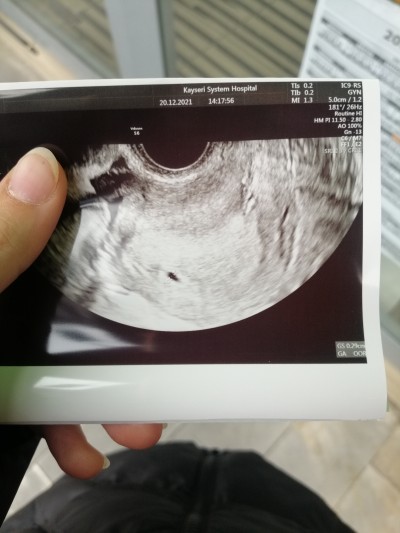

Kızlarr şuan adetin ilk gününden hesaplarsak 5+1 haftalık ama normalde 4 haftalık tas catlasın bugün doktora gittik kese göründü ama küçük 4 haftalık oldugu içinmi  10 gün sonrada kalp atışı dedi duyulur mu daha cok küçük degilmi ya gittiğimde duyamazsam cok korkuyorum bi düşüğüm oldugu için

Gebelik haftası 5

Bende koydum resmini bakabilirmisiniz normal demi korkudan kndimi ikna edemiyorum

Yok canım gayet normal şöyle ki hatta senin kese ml olarak benimkinden büyük bile merak etme :) resimleri baz alma çünkü senin ki daha geniş almış ultrasonu minik duruyor  kesen,  benim ki çok yakınlaştirip almış ondan büyük gibi duruyor .